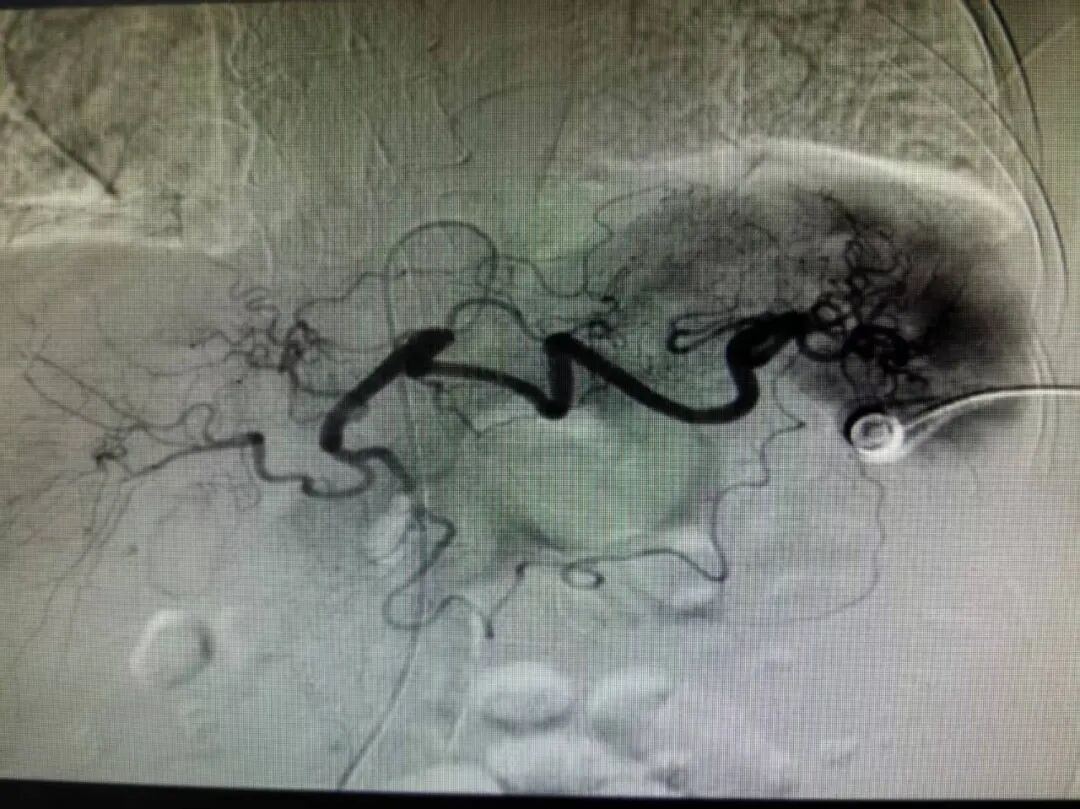

介入治疗

患者情况危急,救治刻不容缓。廉医消化内科介入团队秉持救死扶伤的医者仁心,建议实施急诊介入止血治疗。一开始患者及家属抱有怀疑态度迟迟没有下定决心,经过消化内科介入团队的详细介绍和耐心细致沟通,患者及家属最终接受这一治疗方案。消化内科介入团队凭借熟练过硬的技术,及时行急诊介入治疗,成功栓塞血管预防再出血。经过紧张的救治,患者成功转危为安,并于3月17日顺利出院。出院后,患者及家属特地送来锦旗以表示对廉医消化内科团队的肯定和感谢。此次成功救治急性上消化道大出血高龄患者,不仅是对消化内科团队专业能力的有力证明,更为面临同样危急重症的患者带来了生的希望。